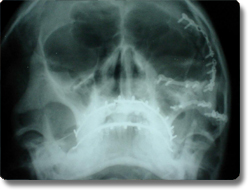

面部不留疤痕治疗上、下颌骨等面部骨折

在面部复杂骨折的治疗中,如何做到既使所有的骨折断端良好复位固定,又不在面部遗留手术切口,仍是治疗中的难题。以往上、下颌骨骨折的手术内固定均采用面部或颌下区皮肤切口入路方法治疗,面部遗留疤痕,影响美观。我科目前采用经头部冠状切口、口腔内切口入路的手术途径暴露伤区,用微型钛合金固定板固定骨折段,既良好的治疗骨折,保证口腔及上、下颌骨功能,又可维持面部外形,面部不留疤痕。我科在重庆市首家开展该方法治疗,与国际最先进水平保持同步。